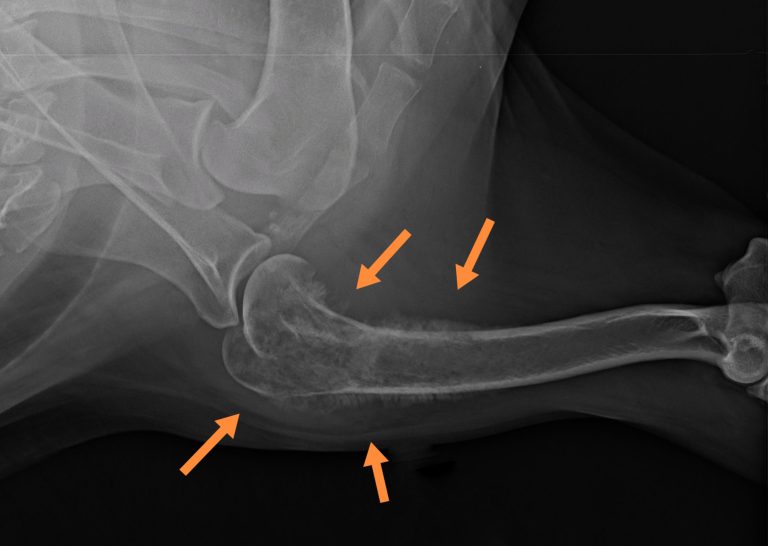

Krónikus, gyógyszerrezisztens sántaságnál, tapintható csontkemény duzzanat esetén a régió röntgenvizsgálata javasolt első körben. Az osteosarcoma (vagy más csontdaganat) esetén a csontok állománya felhőszerűen megritkul, a röntgeneken kissé molyrágtának tűnik, ezzel egyidejűleg a külső felszínen csontfelrakódások is kialakulnak, a csonthártya pedig sokszor elemelkedik, ami nagyon jellemző az osteosarcomára.

Erősen meggyengült csontszerkezet esetén annak patológiás törése, beroppanása is látható lehet. A röntgenfelvételeken látható csontoldódással járó elváltozások fertőző- vagy rosszindulatú folyamatra utalnak, ezért minden esetben további diagnosztikai vizsgálatok javasolhatók.